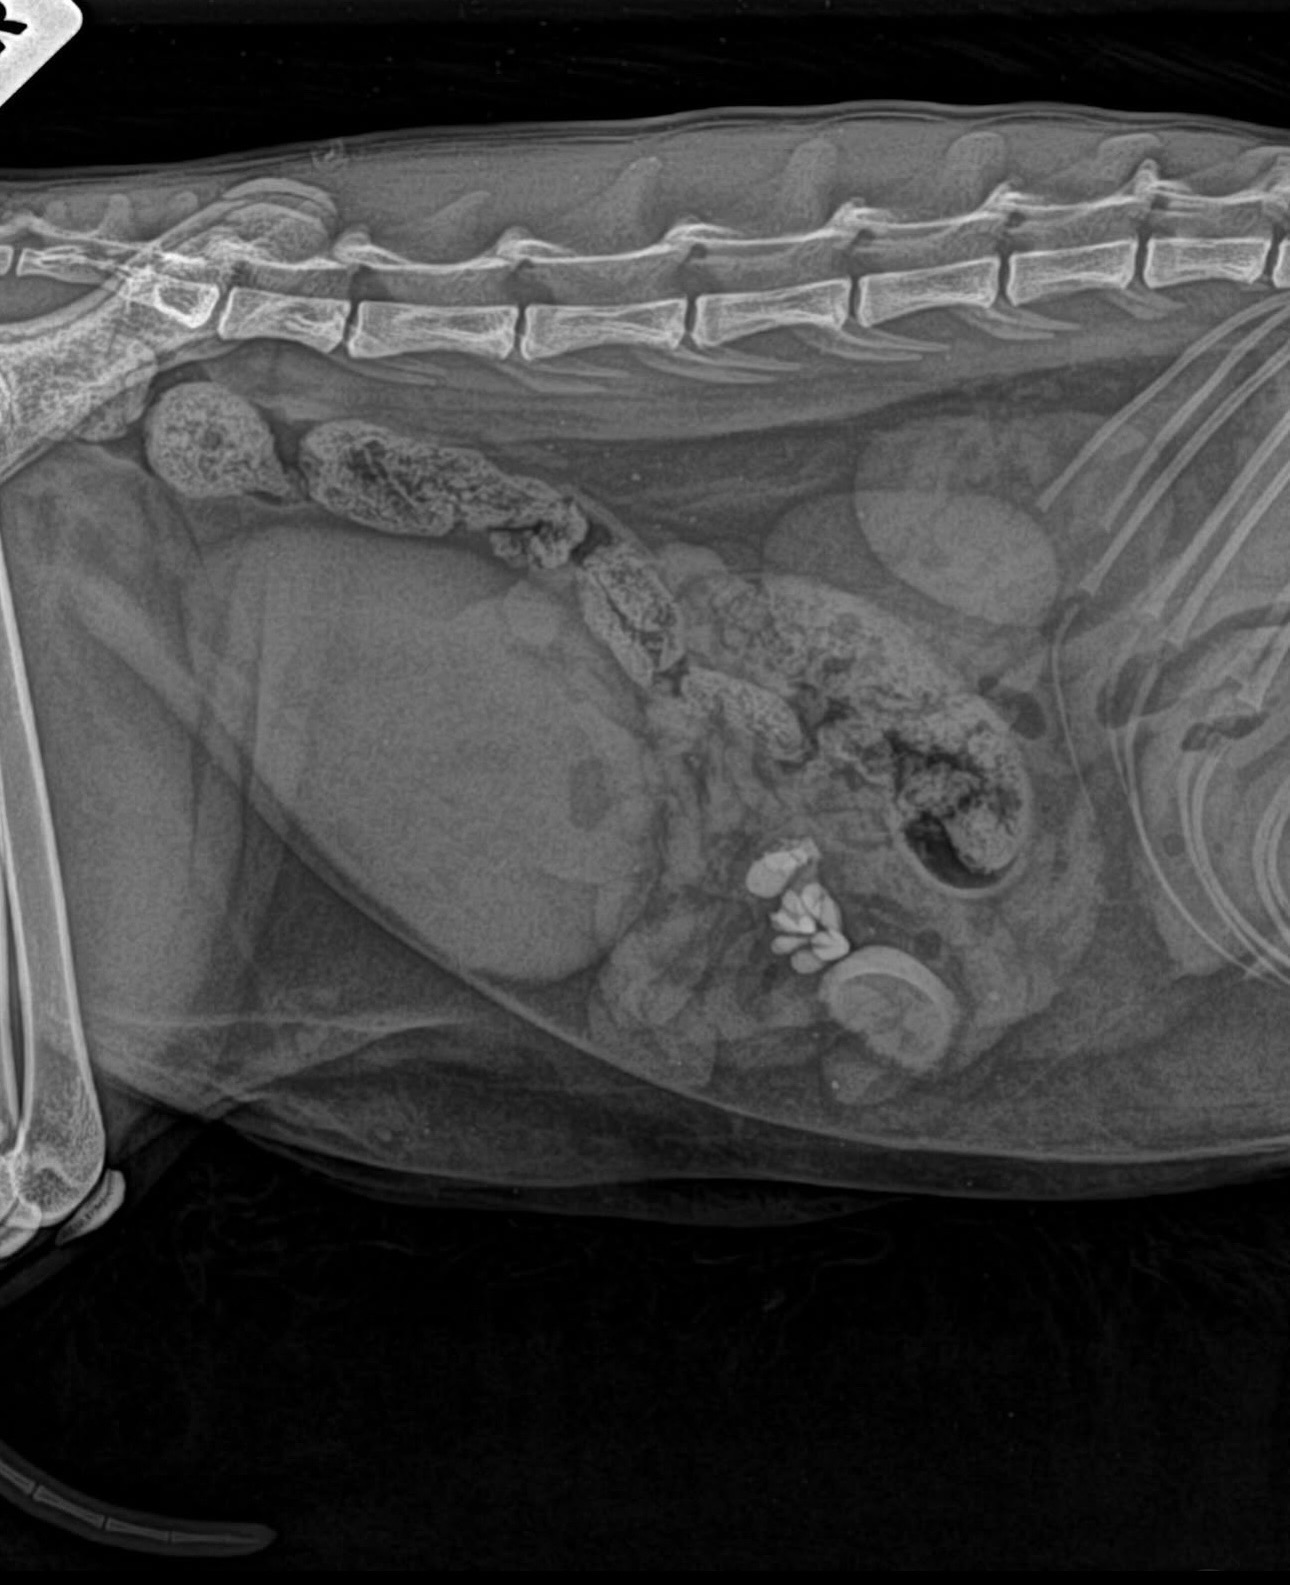

That’s when the vets discovered a life-threatening bowel obstruction.

They told me Love needed emergency surgery immediately to remove the blockage, as they feared he wouldn’t make it through the night otherwise.

During surgery, they found silicone pieces from a chew toy, along with part of the artificial plant, lodged in his intestines. These had been swallowed at some point and caused the blockage.